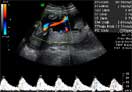

La imagen de la ecografía en 4D ha captado a este feto de 19 semanas de gestación moviendo sin parar sus brazos y piernas. Sus extremidades inferiores y superiores ya tienen una longitud acorde al resto de su cuerpo.

En este vídeo podemos apreciar a un bebé de 19 semanas con todos los miembros en activo, imágenes muy apreciadas por los especialistas. Junto al movimiento de brazos y piernas, se aprecia perfectamente el cordón umbilical.